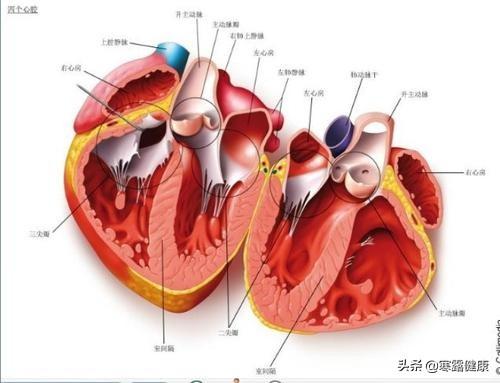

Tous les types de maladies cardiaques conduisent inévitablement à deux conditions : une activité électrique instable ou perturbée du cœur (arythmie) et une activité mécanique altérée du cœur (insuffisance cardiaque).

2. difficulté à respirer la nuit.Certains patients souffrant d'insuffisance cardiaque peuvent présenter des paroxysmes nocturnes de dyspnée dus à la position du corps, à l'augmentation du flux sanguin de retour et à l'excitation vagale. Certains patients souffrant de maladies respiratoires peuvent également présenter une oppression thoracique, qui doit être différenciée du BNP/NT-proBNP et de l'échographie cardiaque.

3. la respiration assise la nuit.Les patients souffrant d'une insuffisance cardiaque gauche plus grave ne peuvent dormir qu'assis la nuit, et lorsqu'ils s'allongent, ils ont des difficultés à respirer et à prendre l'air.

4. insuffisance cardiaque gauche aiguë.Chez certains patients souffrant d'une maladie coronarienne, la nuit, en particulier la fin de la nuit, est la période la plus propice aux épisodes d'insuffisance cardiaque, et une insuffisance cardiaque gauche aiguë peut survenir dans les cas graves, voire menacer le pronostic vital.

Les principales affections cardiaques susceptibles d'affecter le sommeil sont l'insuffisance cardiaque, l'arythmie, l'angine de poitrine, etc.

1) Dyspnée paroxystique nocturne : les patients souffrant d'insuffisance cardiaque gauche chronique peuvent être réveillés brusquement en raison d'un essoufflement et contraints de s'asseoir, ce qui peut être soulagé par le repos.

2) Respiration assise : l'insuffisance cardiaque gauche chronique peut entraîner une stase pulmonaire ; dans une certaine mesure, le patient ne peut pas s'allonger pour dormir, mais seulement prendre la position de l'oreiller haut, la position semi-allongée ou même la position assise, ce qui peut être amélioré.

3. toux, expectoration : les patients souffrant d'insuffisance cardiaque chronique gauche toussent, expectorent, au début, souvent la nuit, crachent des expectorations mousseuses de pulpe blanche, et parfois du sang dans les expectorations.